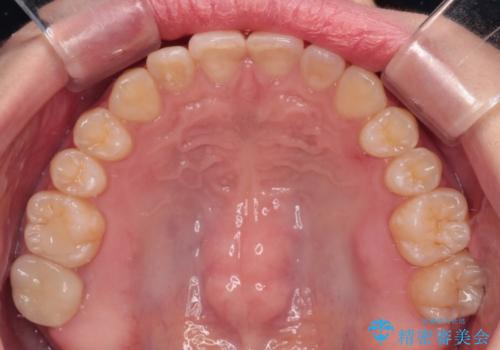

治療途中の奥歯と矯正治療の後戻り インビザライン・ライトによる矯正治療

- 根管治療を行ったままの奥歯と、矯正治療の後戻りを気にして来院された患者様です。

根管治療された歯に症状はなく、オールセラミッククラウンにて補綴治療を行うこととしました。

矯正治療の後戻りは軽微であったため、インビザラインの簡易パッケージであるインビザライン・ライトを用いて歯列を整えることとしました。

クラウンはよりよい咬み合わせで装着したいため、インビザラインを1セット使用して概ね歯列を整えた時点で補綴治療を行い、その後仕上げの矯正治療を行いました。